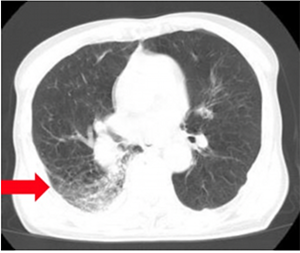

肺炎

精密検査を行って長引く咳を診断・治療します。

風邪の診断でも、なかなか咳が治まらないときは、肺炎をおこしている場合があります。